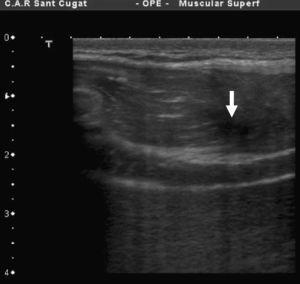

A pesar de los 7 días transcurridos, se observa una disrupción del correcto patrón fibrilar con sufusión hemática que invade la totalidad de la lesión y edema perilesional (figura 1, figura 2). El examen ecográfico también mostró una imagen fibrosa que, una vez interrogado el paciente, se concluyó que correspondía a una lesión antigua en el mismo vientre y asintomática en el momento de la consulta (figura 3).

Figura 1. Imagen ecográfica transversal de la lesión localizada en la zona próxima a la aponeurosis profunda a la derecha de la imagen.